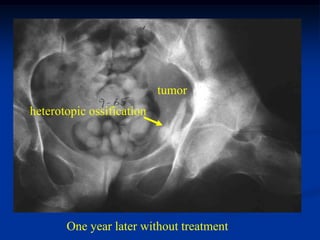

Case #1161             Endometrial CA

54 year female with endometrial CA uterus to pelvis

tumor

heterotopic ossification

One year later without treatment